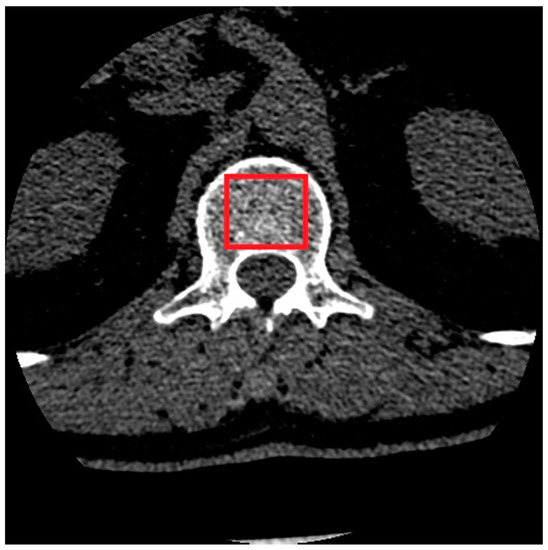

2.1. Material

2.2. Image Preprocessing

2.3. Estimation of Texture Parameters